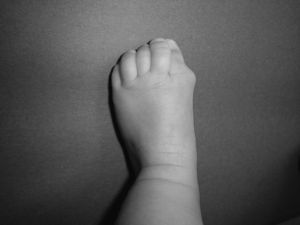

Los recién nacidos con FOP tienen un aspecto normal excepto por la presencia (en la práctica totalidad de ellos) de malformaciones en el dedo gordo del pie, siendo el hallux valgus congénito el sello más característico de la enfermedad (fig. 1)13,14. Aunque se suelen reconocer más tarde (e incluso pasan inadvertidas o son erróneamente interpretadas), el componente displásico de la FOP se puede manifestar por diversas anomalías esqueléticas congénitas que aparecen con una frecuencia variable pero casi siempre elevada. Entre estas malformaciones destacan: otras anomalías en los dedos de las manos y los pies distintas de las del dedo gordo del pie (acortamiento de falanges, metatarsianos y metacarpianos, sinostosis, clinodactilia)15; aumento de tamaño y fusión de la facetas posteriores con hipoplasia del cuerpo vertebral en la columna cervical (fig. 2), que puede acabar formando un bloque16–18; osteocondromas, sobre todo evidentes en la región medial de la tibia19, y cuello femoral corto y ancho20.